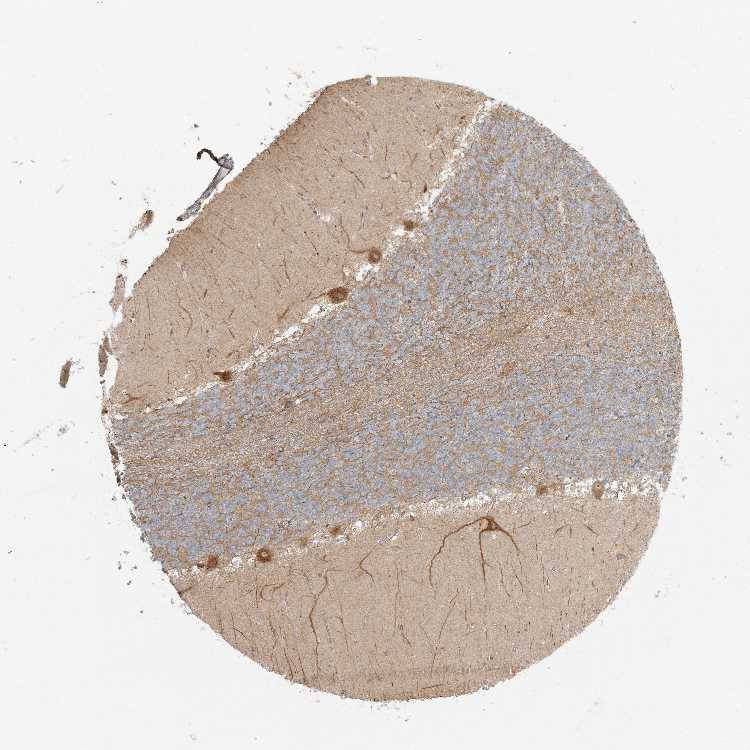

BRAIN CEREBELLUM Show tissue menu

CEREBELLUM - Antibody stainingi

Antibody staining in the annotated cell types in the current human tissue is reported as not detected, low, medium, or high, based on conventional immunohistochemistry profiling in selected tissues. This score is based on the combination of the staining intensity and fraction of stained cells.

Each image is clickable and will lead to virtual microscopy that enables deeper exploration of all samples and also displays staining intensity scores, fraction scores and subcellular localization as well as patient and tissue information for each sample.

Antibody HPA035863

Purkinje cells High

Cells in granular layer Medium

Cells in molecular layer Not detected